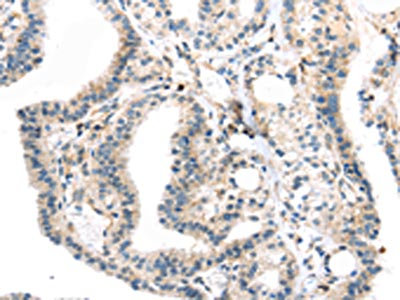

The image on the left is immunohistochemistry of paraffin-embedded Human thyroid cancer tissue using CSB-PA550037(TBXA2R Antibody) at dilution 1/40, on the right is treated with synthetic peptide. (Original magnification: ×200)